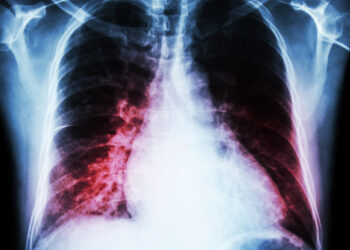

Eozinofilijos-mialgijos sindromas (EMS) – tai retas sutrikimas, kuris pažeidžia raumenis, odą ir plaučius. Ši būklė dažniausiai pasireiškia raumenų skausmu, odos...